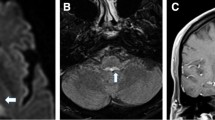

A 63-year-old man presented with dizziness, dysarthria, and unsteadiness that had worsened over the preceding 2 years. The patient had a diagnosis of rapid eye movement sleep disorder and orthostatic hypotension 4 months before. Examination showed no spontaneous or gaze-evoked nystagmus during visual fixation. In darkness without visual fixation, the patient showed spontaneous downbeat nystagmus that increased while lying down and straight head hanging. He also showed paroxysmal vertical oscillation of the eyes without visual fixation, which will be detailed further in the following section. Nevertheless, the patient denied worsening of dizziness with development of paroxysmal vertical oscillation. Smooth pursuit was impaired in both horizontal directions, and saccades were bilaterally hypermetric, but more to the right. Bedsides, horizontal head impulse test was normal in both directions. Visual suppression of the vestibulo-ocular reflex (VOR) was also impaired during en bloc eye-head motion. There was no palatal tremor. The deep tendon reflexes were increased, and coordination was impaired in both the upper and lower extremities. He could maintain balance while standing, but the gait was unstable and wide-based, especially initially, with a gradual improvement during continued gait. Brain MRIs 2 years before showed only mild atrophy of the superior and middle cerebellar peduncles, but follow-up MRIs disclosed prominent and diffuse atrophy in the whole brainstem and cerebellum with a pontine hot cross bun appearance (Fig. 1a, b). Evaluation for cerebellar dysfunction due to para-neoplastic, para-infectious, or other metabolic disorders was unremarkable. The patient was diagnosed with multiple system atrophy (MSA).

MRIs and saccadic oscillations of the patient. The initial (a) and follow-up MRIs (b) with a 2-year interval show progressive atrophy involving the brainstem and cerebellum with an interval development of the hot cross bun appearance. Vertical ocular oscillations (c) follow the downbeat nystagmus only in darkness. The amplitude and velocity profile of the ocular oscillations (d) fit into the amplitude-velocity relationship (main sequence) of normal saccades. RH/LH, right/left eye horizontal; RV/LV, right/left eye vertical